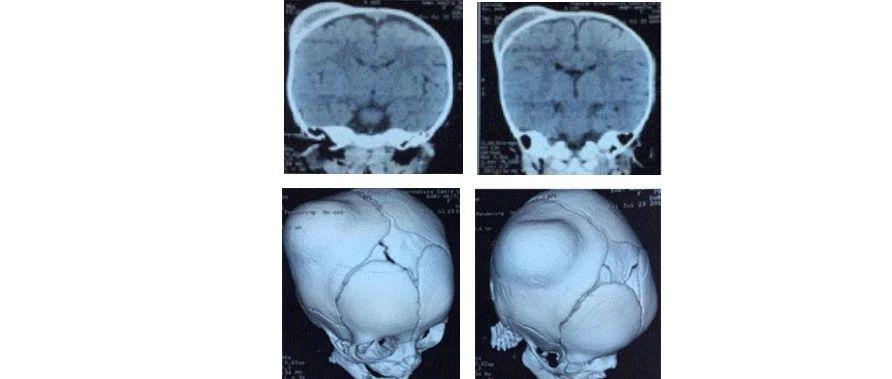

小明出生时,头上就有一个软软的鼓包。医生告诉小明的父母,这是常见的新生儿头皮血肿,通常会自行吸收。然而,几周后,这个鼓包不仅没有消失,反而变得越来越硬,就像头上长出了一个“犄角”。焦急的父母带着小明来到小儿神经外科,医生告诉他们,小明的头皮血肿已经发生了骨化。

大多数新生儿头皮血肿是无害的,会随着时间自行吸收。然而,约3%-5%的头皮血肿可能会发生骨化。这种情况下,血肿中的血液逐渐被钙盐沉积所取代,形成硬化的骨质。骨化通常发生在出生后5周左右,但也有极少数病例在2-3周内就开始骨化。

头皮血肿骨化不仅影响外观,还可能对婴儿的健康造成潜在威胁。大面积的骨化可能压迫正常颅骨,导致头颅畸形。更严重的是,骨化过程可能侵蚀颅骨,影响大脑的正常发育。因此,及时发现和处理头皮血肿骨化至关重要。

3. 手术治疗:如果血肿已经发生骨化,可能需要手术切除硬化部分,以恢复头颅正常形态。